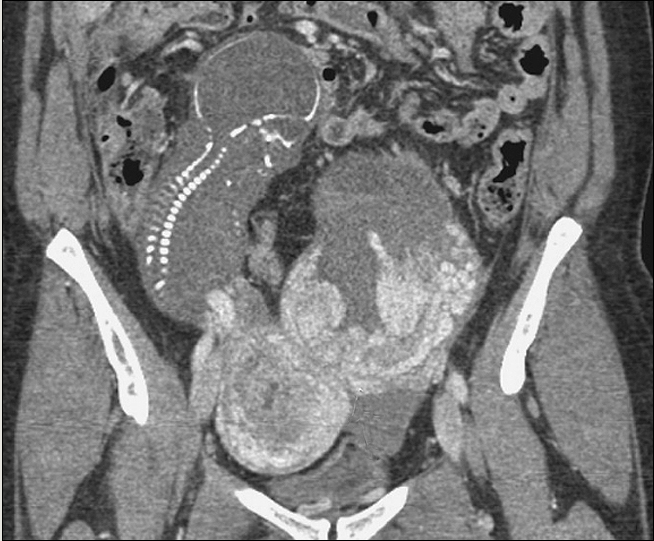

Анатомия и риски внематочной беременности: возможные локализации